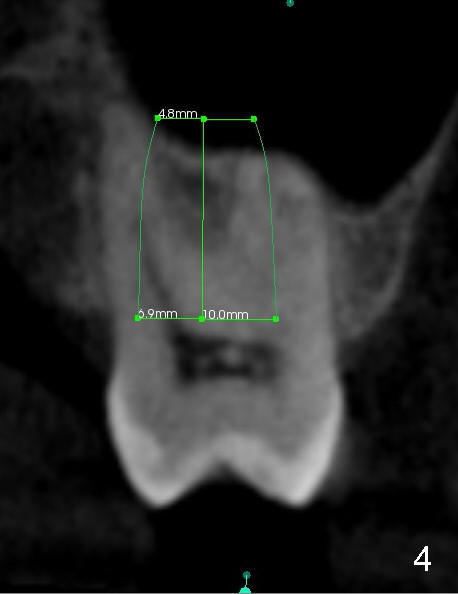

When the buccal roots are fused, there are 3 potential sites for immediate implant (Fig.1'): septum (*), buccal (B) and palatal (P) sockets. Septal placement (6.9x8 mm bone level implant) is the most ideal for restoration (Fig.3). The length of the implant can be increased (10 mm) with sinus lift so that the base of the implant between the buccal and palatal apices in height (Fig.4). Primary stability is derived mainly from the implant body engagement into the septum (Fig.5 coronal section through the septum). If bone density in the septum is high, a small implant may be appropriate (Fig.6,7: 6.4x8 mm). The large implant (6.9 mm) is chosen so that amount of bone graft to be used (Fig.8 red circles) is less.